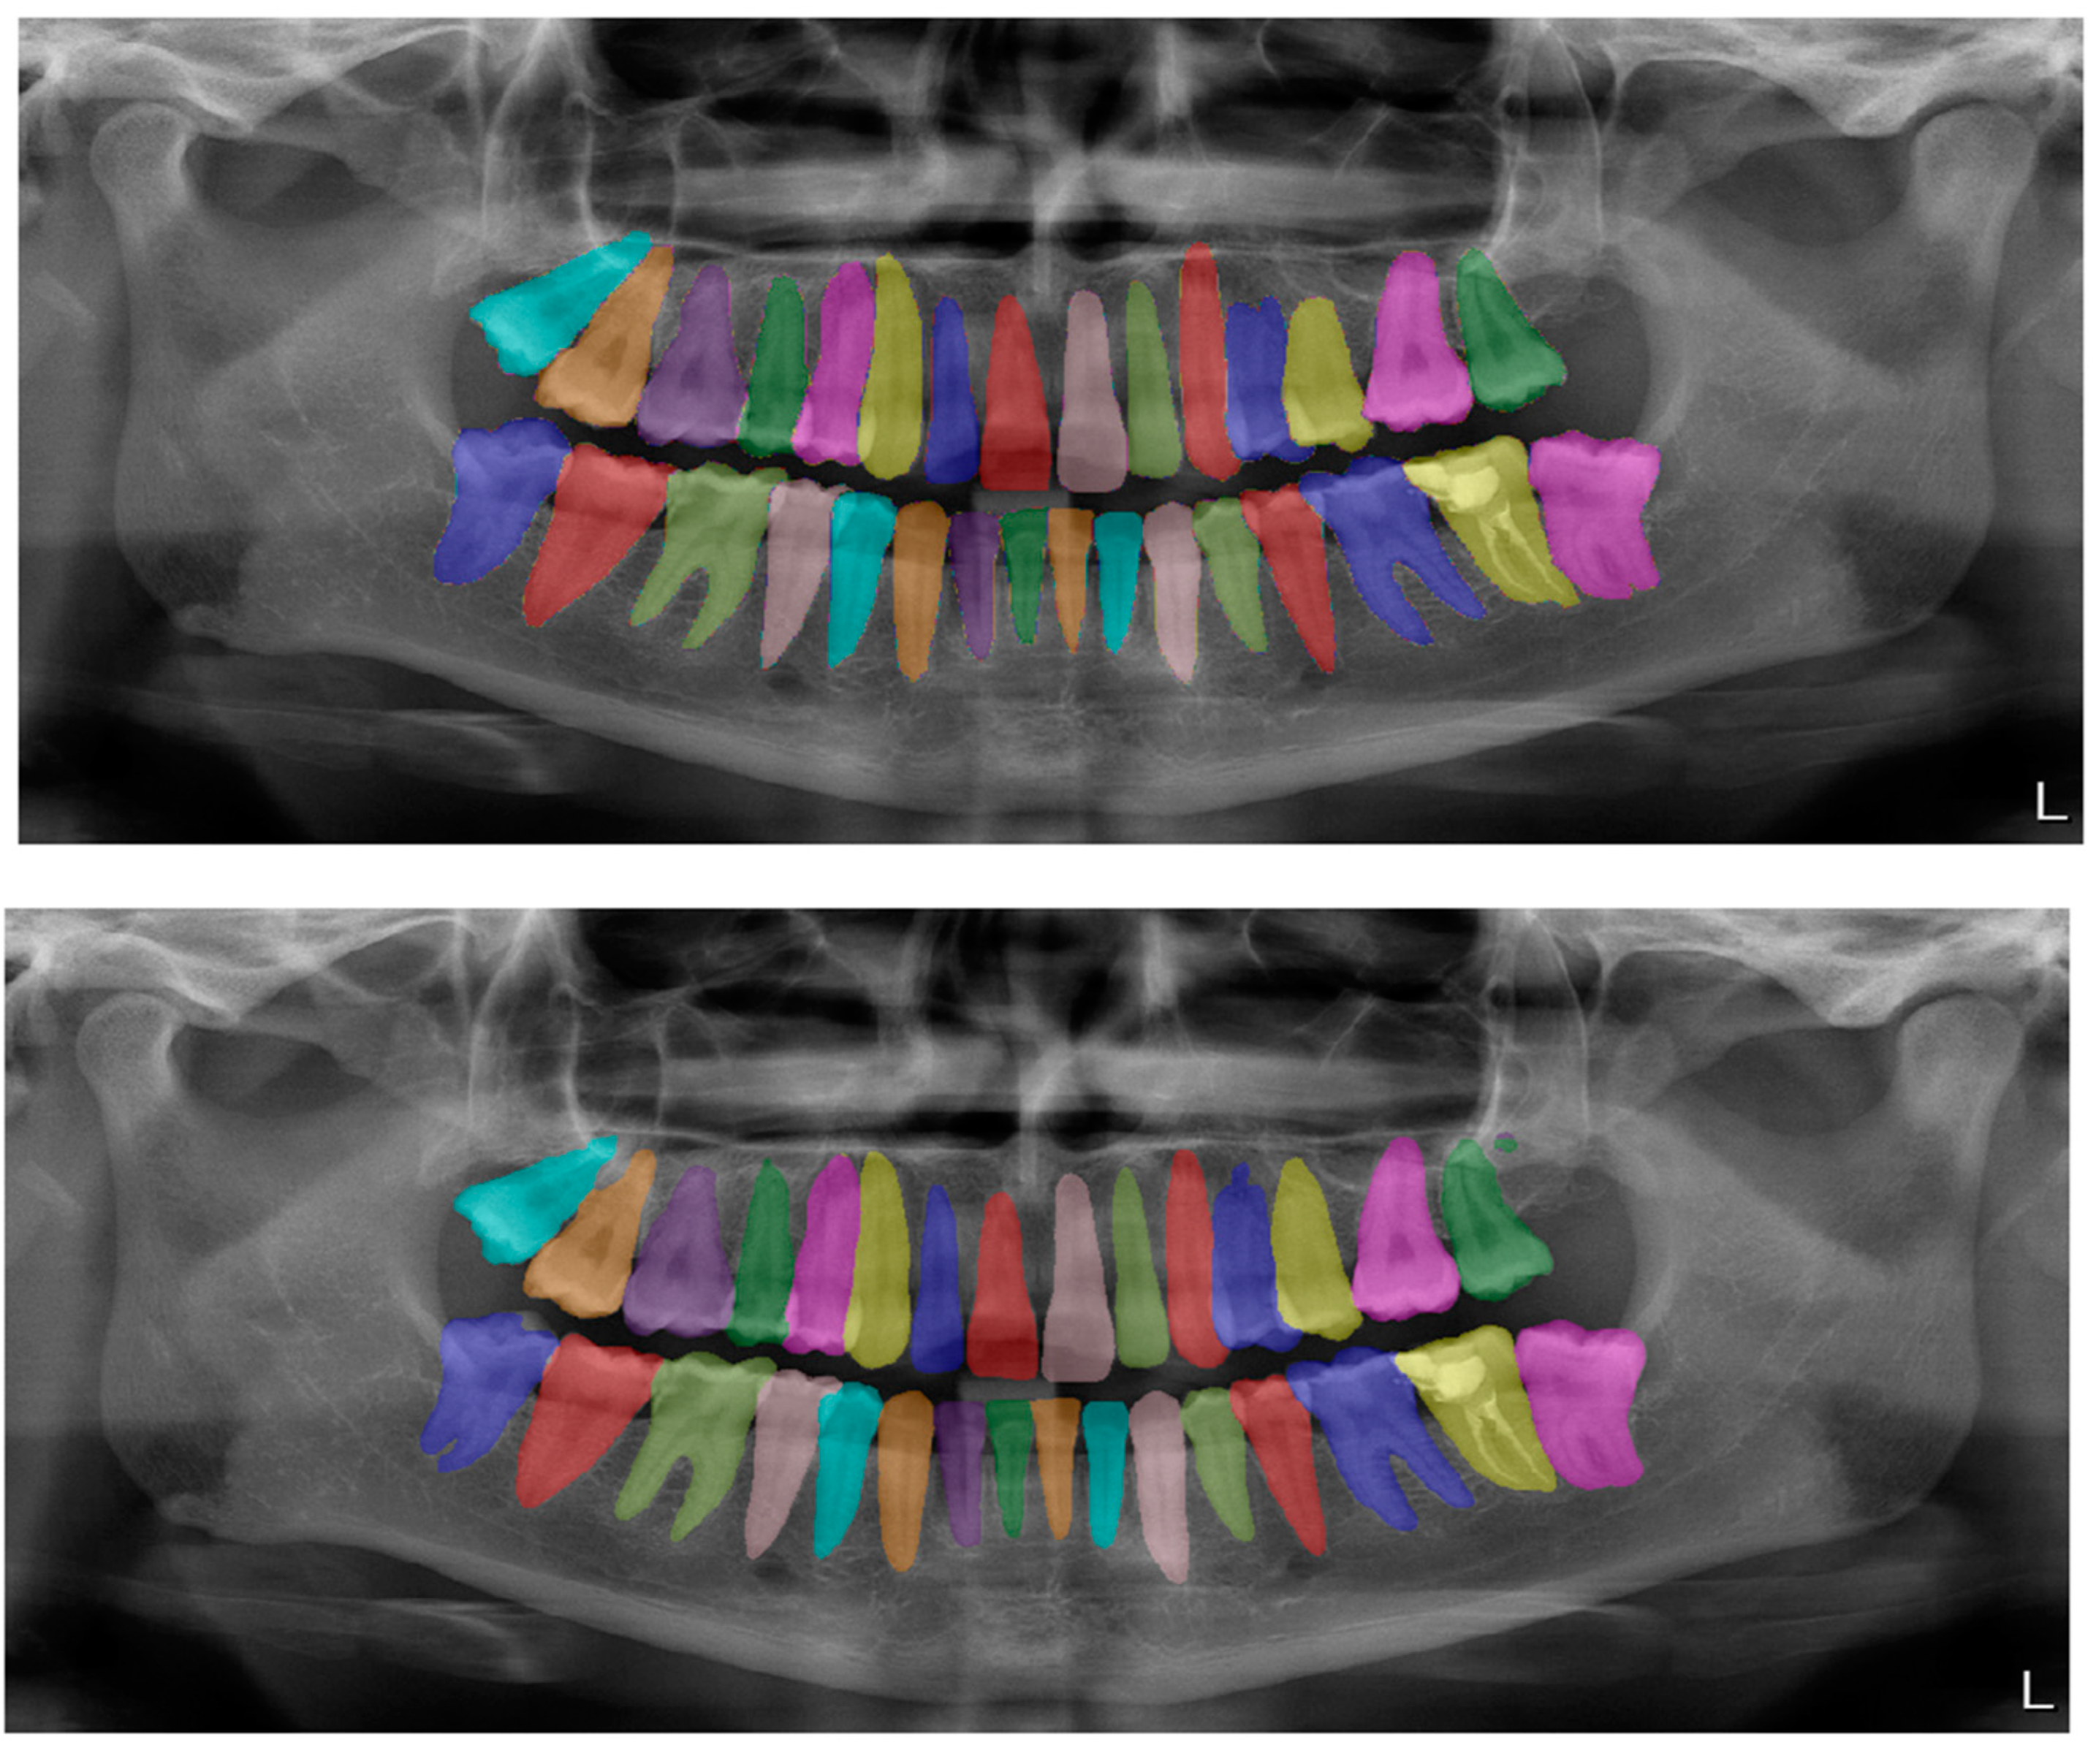

| Structure | DSC |

|---|---|

| Tooth segmentation (Figure 2) | 0.95 |